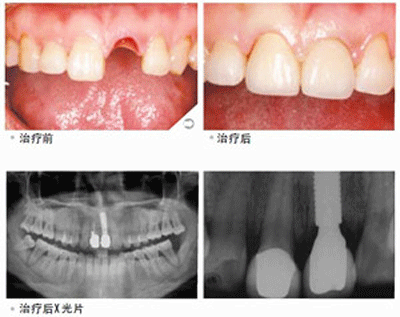

患者的口腔状况良好,牙槽骨状况适合做种植牙。因为种植牙是把人工牙根植入牙槽骨内来代替真牙牙根,然后在人工牙根上制作烤瓷牙冠,完成时对缺失牙齿的修复的。如果患者的牙槽骨状况不佳的的话,比如牙槽骨的宽度和高度不够的话则需要考虑做植骨手术。点这里,直接预约医生!方便快捷!

(1)单颗缺牙时不需要磨损两侧真牙,单颗牙种植体值入后,以烤瓷牙冠修复,特别是末端游离的后牙,传统的固定和活动义齿均难以修复;(2)多颗缺牙,多颗牙种植体植入后,上部烤瓷牙整体修复,稳定性和功能与真牙相似。(3)全口缺牙,多颗牙种植体植入后,当做支柱,以制作覆盖义齿,使其很稳定舒适。